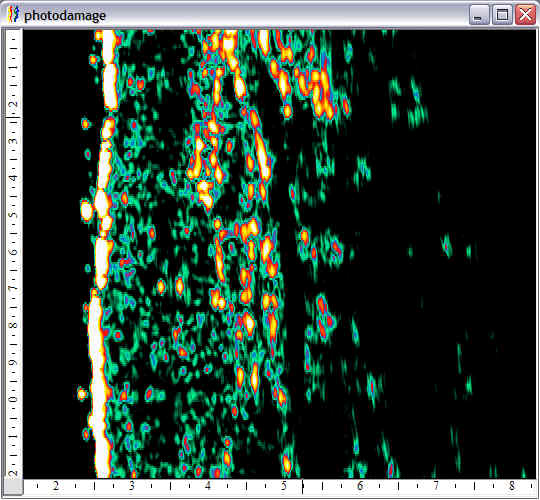

Face, minor photoaging |

Face, major photoaging |